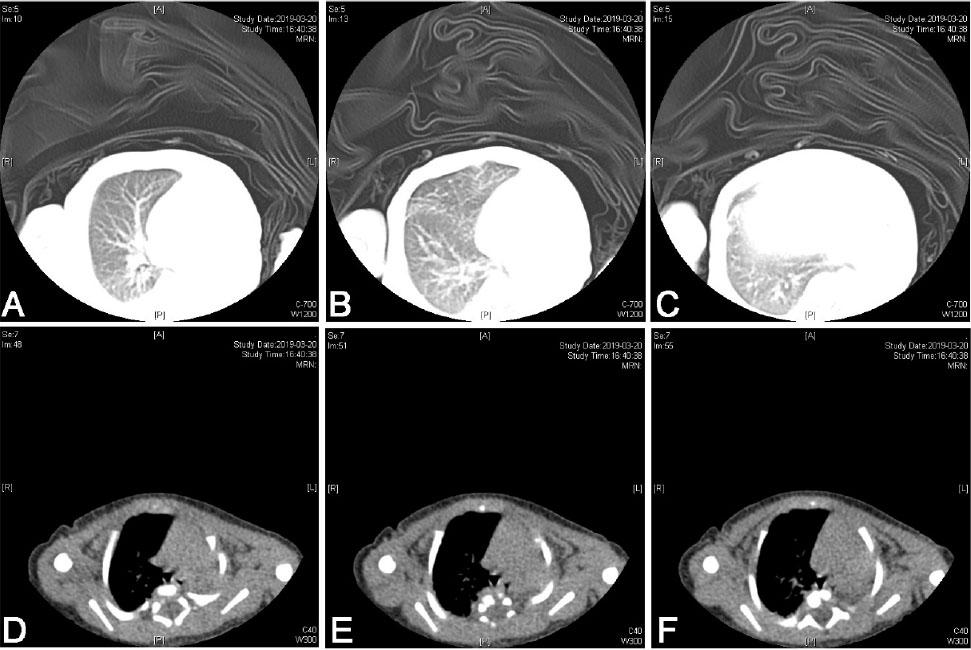

As she showed accelerated breathing, a conventional physical examination was given. There was no respiratory sound in the left lung according to auscultation. Chest film indicated decline in lucency of left lung (Figure 1). Thoracic CT scan was recommended as the size of reduced pulmonary lucency in chest film was too large (Figure 2). On day 3, thoracic CT and pulmonary window indicated absence of left lung and primary bronchus in the left lung. For mediastinal window, there was mediastinal shift to the left side. Structural boundary within left mediastinum was not completely displayed. Three-dimensional imaging indicated extension of trachea, right principal bronchus and bronchus into right lung lobe, while the left lung and left principal bronchus were not visualized (Figure 3). Cardiac ultrasonography confirmed congenital heart disease presenting ventricular septal defect (VSD, 0.18 cm), patent ductus arteriosus (PDA, 0.3 cm × 0.2 cm), patent foramen ovale (0.28 cm), pulmonary hypertension (43 mmHg), mild to moderate tricuspid regurgitation, as well as slight pericardial effusion. Moreover, she showed ectopic kidney. Finally, she was diagnosed with CPH combined with congenital cardiac disease and ectopic kidney.

Thoracic CT indicated that the left lung and the primary bronchus of left lung were not available in pulmonary window. No shadows with aberrant densities were noticed in the right lung (A–C). In addition, there was mediastinal shift to left side in mediastinal window. The structures and boundaries in left mediastinum were not completely displayed (D–F).